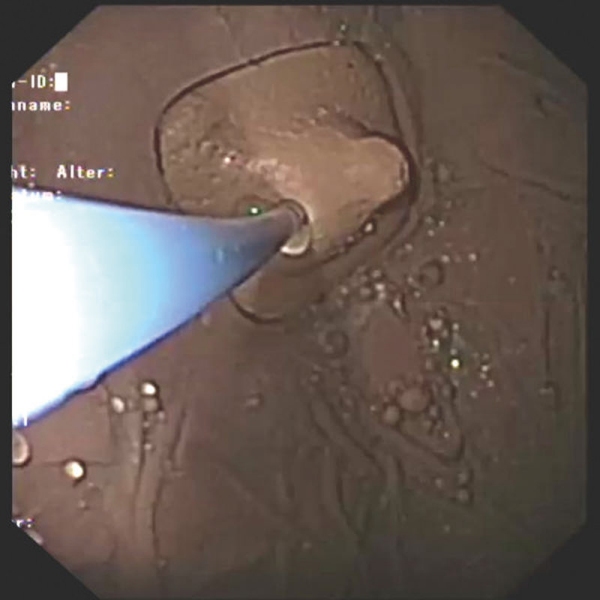

- Vadba vbrizgavanja tkiv

- Zdravljenje krvavitev / zaustavljanje krvavitev z injekcijami, sponkami in ligiranjem traku